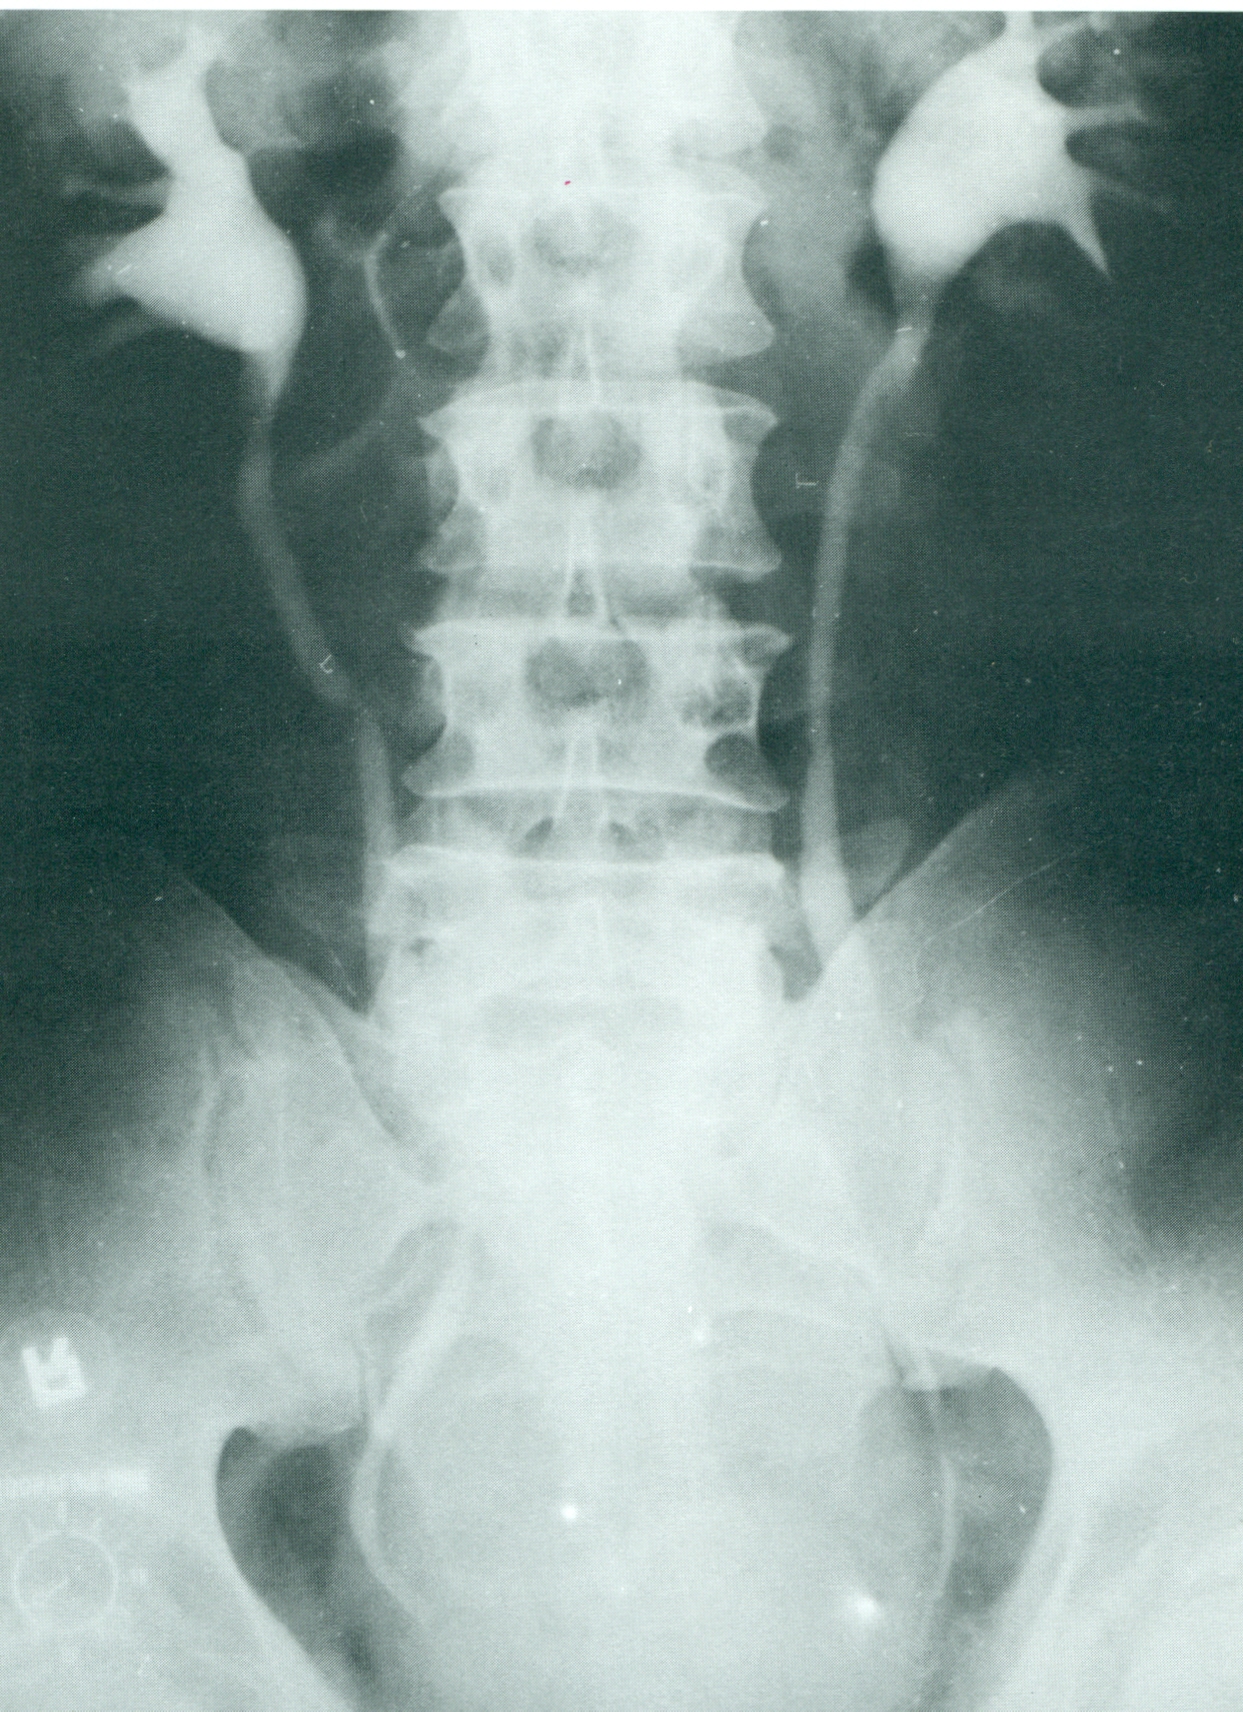

Urografía normal.

Los uréteres no son visibles sobre todo su

longitud.